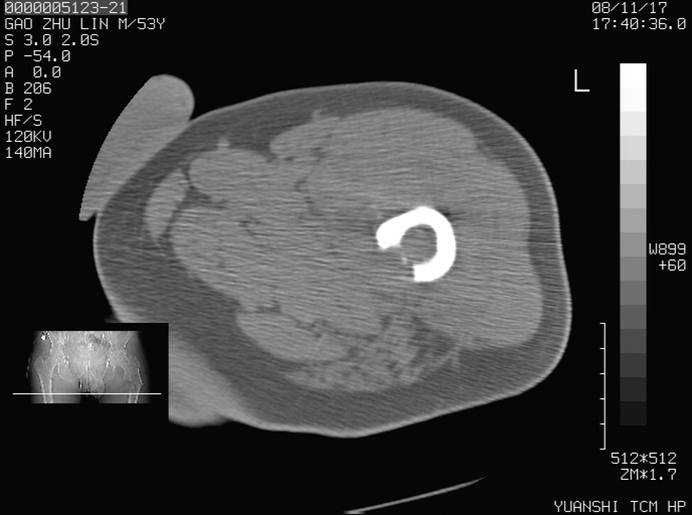

标题: CT16696:M53Y,左股骨上段骨折。 [打印本页]

标题: CT16696:M53Y,左股骨上段骨折。

左股骨上段外伤1个小时,左股骨上段疼痛。村医以腰椎间盘病变给以按摩及理疗数天。

图像不太清楚,左股骨上段外伤性骨折?病理性骨折?

左股骨上段粉碎性骨折

左股骨上段粉碎性骨折;建议上传骨窗看看是不是病理性的啊!

左股骨上段粉碎性骨折,不排除病理性骨折可能。

考虑骨肉瘤伴病理骨折

考虑:骨肉瘤伴病理骨折.

病理性骨折,考虑转移所致.

左股骨上段粉碎性骨折,不排除病理性骨折可能